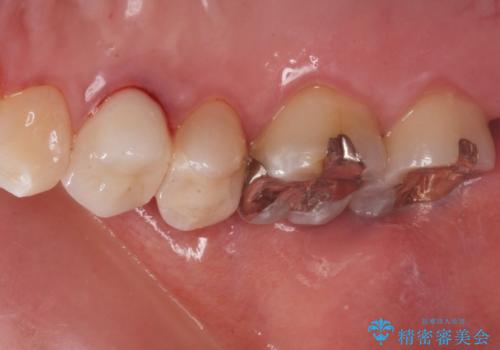

- 奥の歯に穴が空いているとの事で来院。

拡大鏡下で虫歯を全て除去しゴールドインレーにて治療しました。

ゴールドインレーはメタルインレーに比べて、歯と詰め物の隙間が生じにくため

虫歯菌が侵入することなく、虫歯の再発のリスクが低いです。